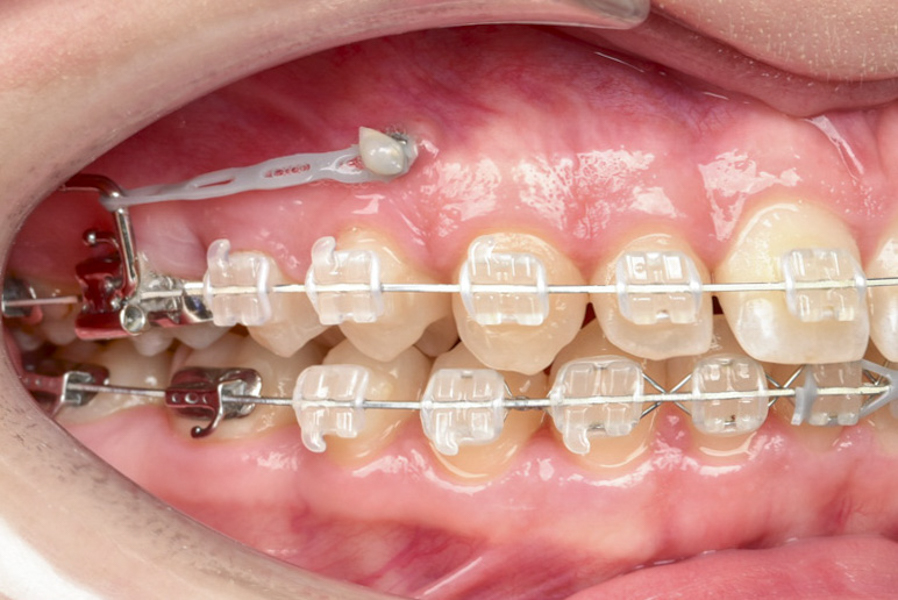

Skuteczna ortodoncja wymaga czasu. Na szczęście dzięki współczesnym, innowacyjnym metodom, które stosujemy w naszej klinice, czas potrzebny do dokonania skutecznej korekty ustawienia zębów można teraz znacznie skrócić. Jednym z takich rozwiązań są miniimplanty ortodontyczne. Te tymczasowe zakotwiczenia mają za zadanie utrzymać jeden lub więcej zębów w ich dotychczasowym położeniu, a równocześnie pomóc w przemieszczeniu innych w zamierzonym kierunku. Do tej pory tego typu procedury były często niemożliwe do przeprowadzenia lub wymagały zabiegów chirurgicznych. Teraz, dzięki miniimplantom, możemy zaprojektować system korekcyjny, który bardzo skutecznie i szybko ustawi zęby w z góry zaplanowanych pozycjach.

Podczas korekcji zgryzu, w szczęce pacjenta montujemy jeden lub więcej miniimplantów. Zabieg jest bardzo precyzyjny, bezbolesny (w miejscowym znieczuleniu komputerowym) i trwa zaledwie kilka chwil. Ze względu na mały rozmiar śruby, pacjenci zazwyczaj nie odczuwają żadnych dolegliwości czy dyskomfortu. Specjalna struktura miniimplantu zapobiega jego integracji z kością, dlatego – kiedy urządzenie spełni swoje zadanie – można je łatwo usunąć.

Miniimplanty pozwalają znacznie skrócić proces leczenia ortodontycznego. Dają też możliwość dokonywania drobnych korekt w pozycji niektórych zębów bez konieczności zakładania aparatu stałego na cały łuk zębowy.